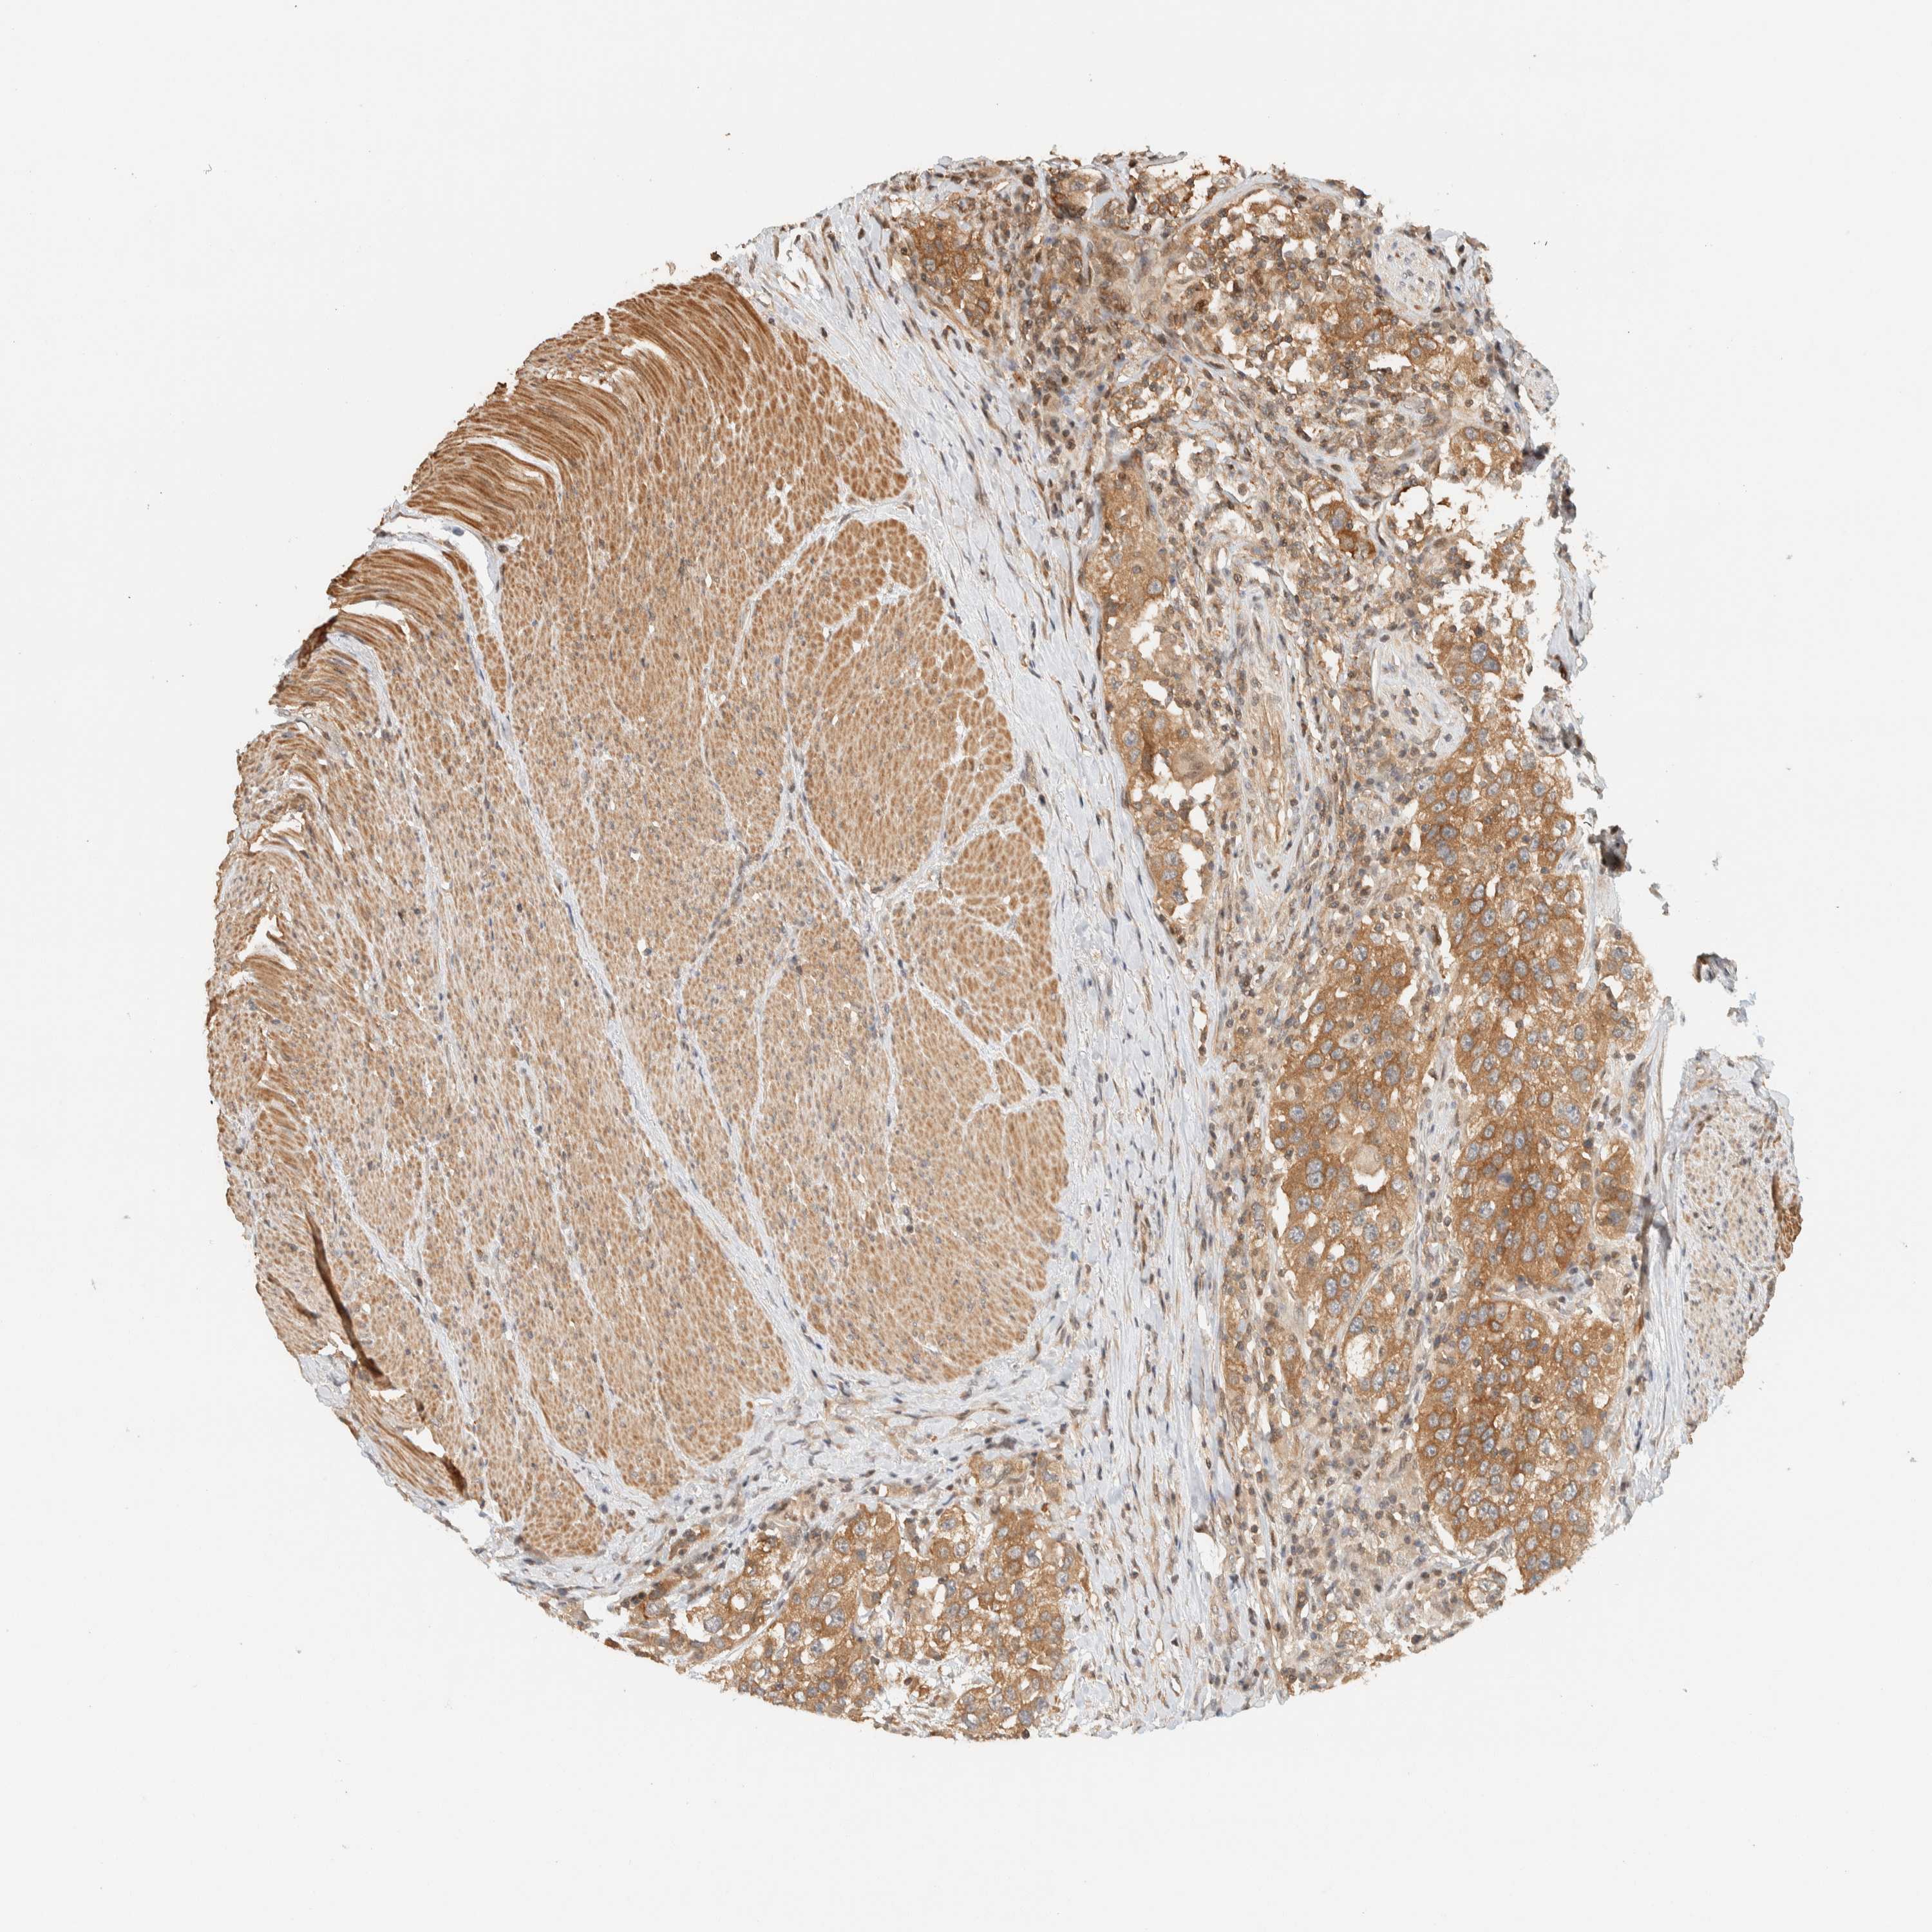

UROTHELIAL CANCER - Protein expressioni

A mouse-over function shows sample information and annotation data. Click on an image to view it in a full screen mode. Samples can be filtered based on level of antibody staining by selecting one or several of the following categories: high, medium, low and not detected. The assay and annotation is described here.

Note that samples used for immunohistochemistry by the Human Protein Atlas do not correspond to samples in the TCGA dataset.

Antibody stainingi

Antibody staining in the annotated cell types in the current human tissue is reported as not detected, low, medium, or high, based on conventional immunohistochemistry profiling in selected tissues. This score is based on the combination of the staining intensity and fraction of stained cells.

Each image is clickable and will lead to virtual microscopy that enables deeper exploration of all samples and also displays staining intensity scores, fraction scores and subcellular localization as well as patient and tissue information for each sample.

Antibody HPA023399

Antibody HPA023822

Urothelial carcinoma, Low grade

Urothelial carcinoma, High grade